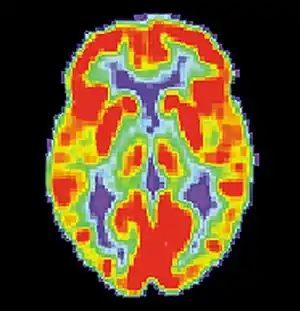

False memories and PET scans

A follow-up to the previous research was conducted by Daniel L. Schacter and colleagues. Similar to the study by Henry L. Roediger and Kathleen McDermott, subjects were read a list of associated words before they went into the PET scanner. During the first scan, subjects would make recognition judgments to determine what were the previous presented words.[2] During the second scan, subjects had to make judgments about words that were not presented. For example: bed, rest, dream, tired, and awake would be in the list but not the word "sleep". As with the study by Henry L. Roediger and Kathleen McDermott, subjects claimed to remember similar amounts of non-presented words as they did the words that were actually presented.[2] The researchers noted that brain activity during the true and false recognition tasks were very similar. Monitoring the blood flow in the brain revealed there were in the left medial temporal lobe for both veridical and illusory recognition.[17]

That is not to say that there were not differences. While monitoring blood flow in the brain during false recognition, a part of the frontal lobe that is thought to be a key monitor of memories actually showed greater activity when presented with a false recognition than with a true one.[2] There seemed to be some discrepancy as subjects attempted to scrutinize the out-placed words, but were overcome by powerful memory illusion.[2] This study demonstrates the ability of technology to help researchers understand to a greater extent the power of false memories.